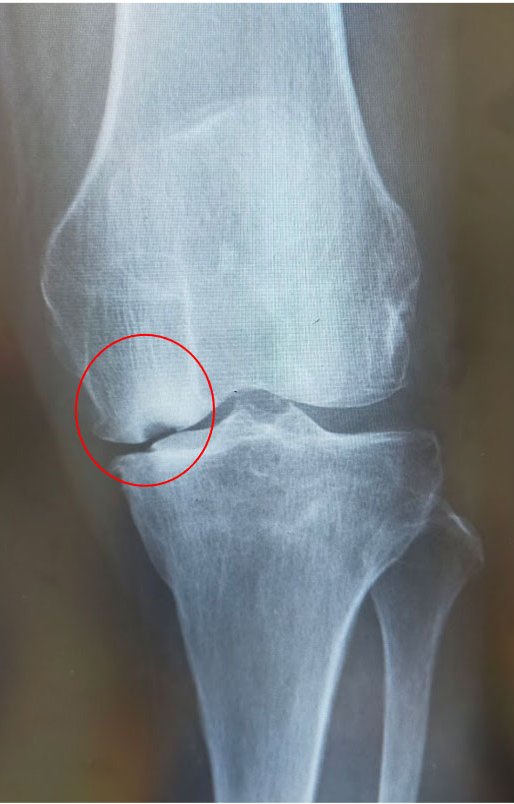

大腿骨顆部は体重を支えるのに重要で、過度なストレスが加わり壊死に陥ることがあります。原因としてステロイド投与や半月板損傷後などに脆弱性骨折(軽微な外傷により軟骨下骨に微小骨折を生じる)が起こり壊死に至るとされています。安静にしていても痛みが出たり、夜間寝ている間に痛みが出ることもあります。

大腿骨顆部骨壊死